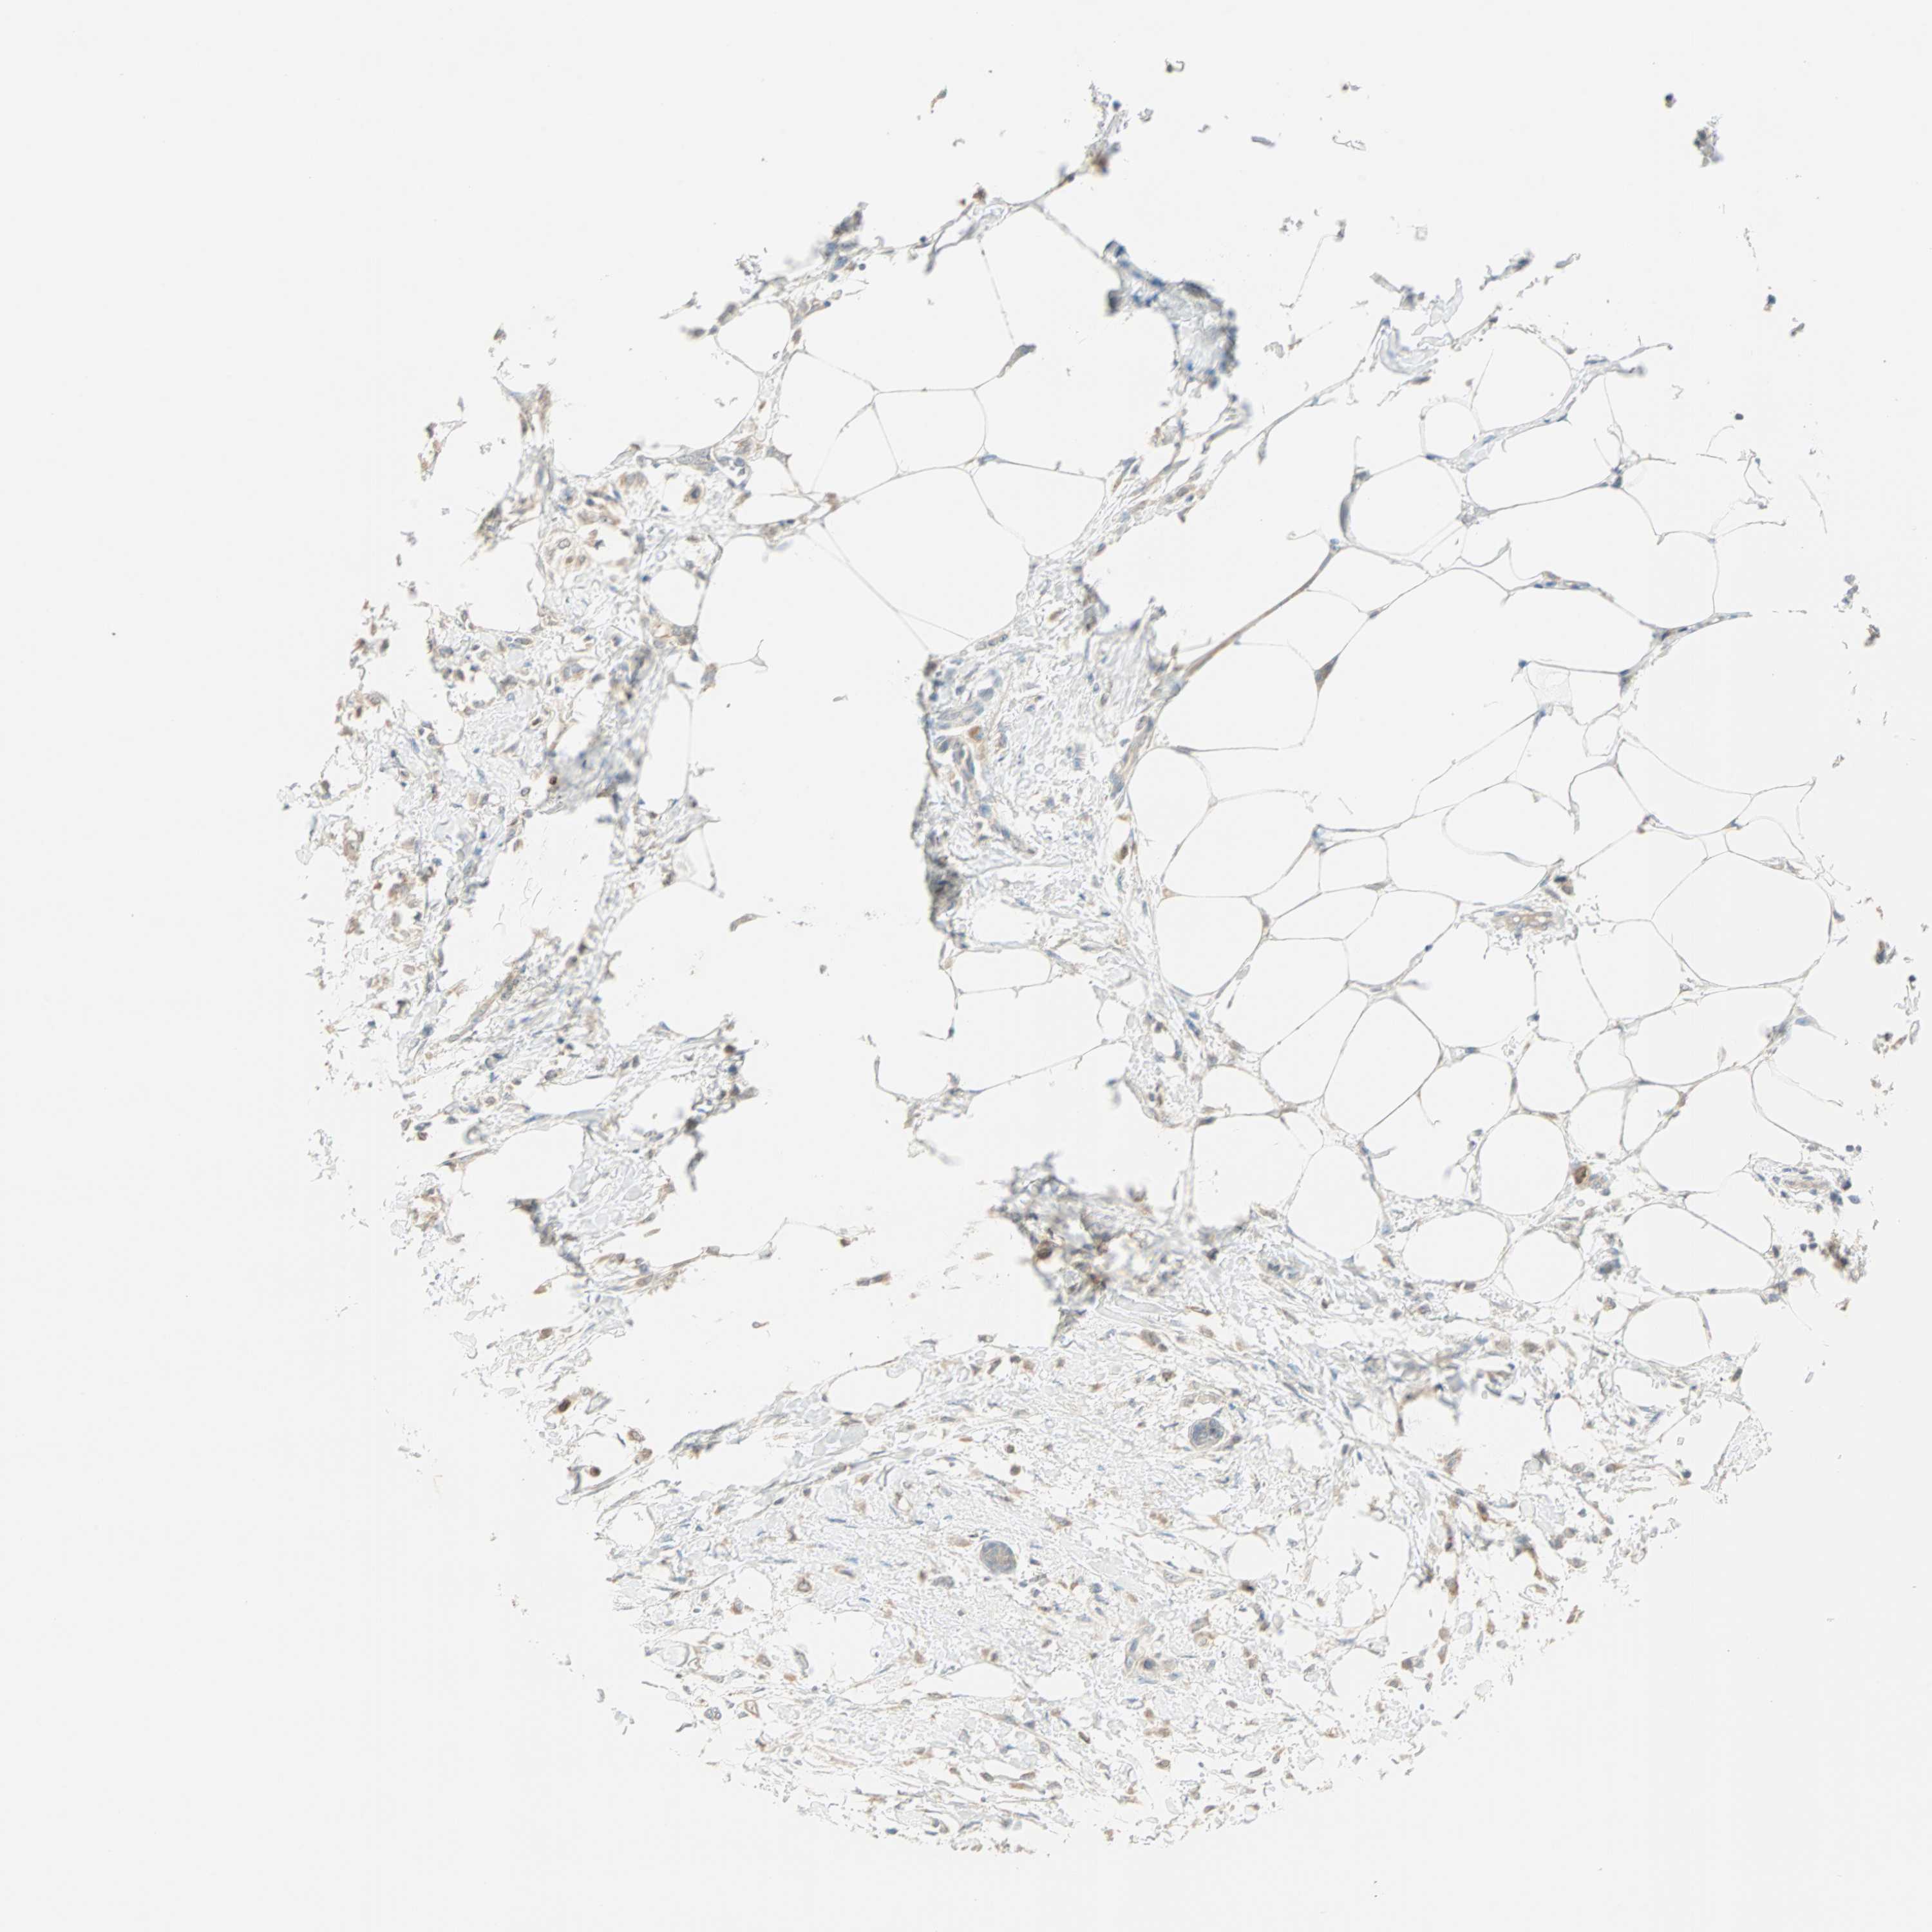

CANCER BREAST CANCER Show tissue menu

BRCA TCGA BRCA VALIDATION PROTEIN EXPRESSION

Breast cancer

Human cancer

Breast invasive carcinoma